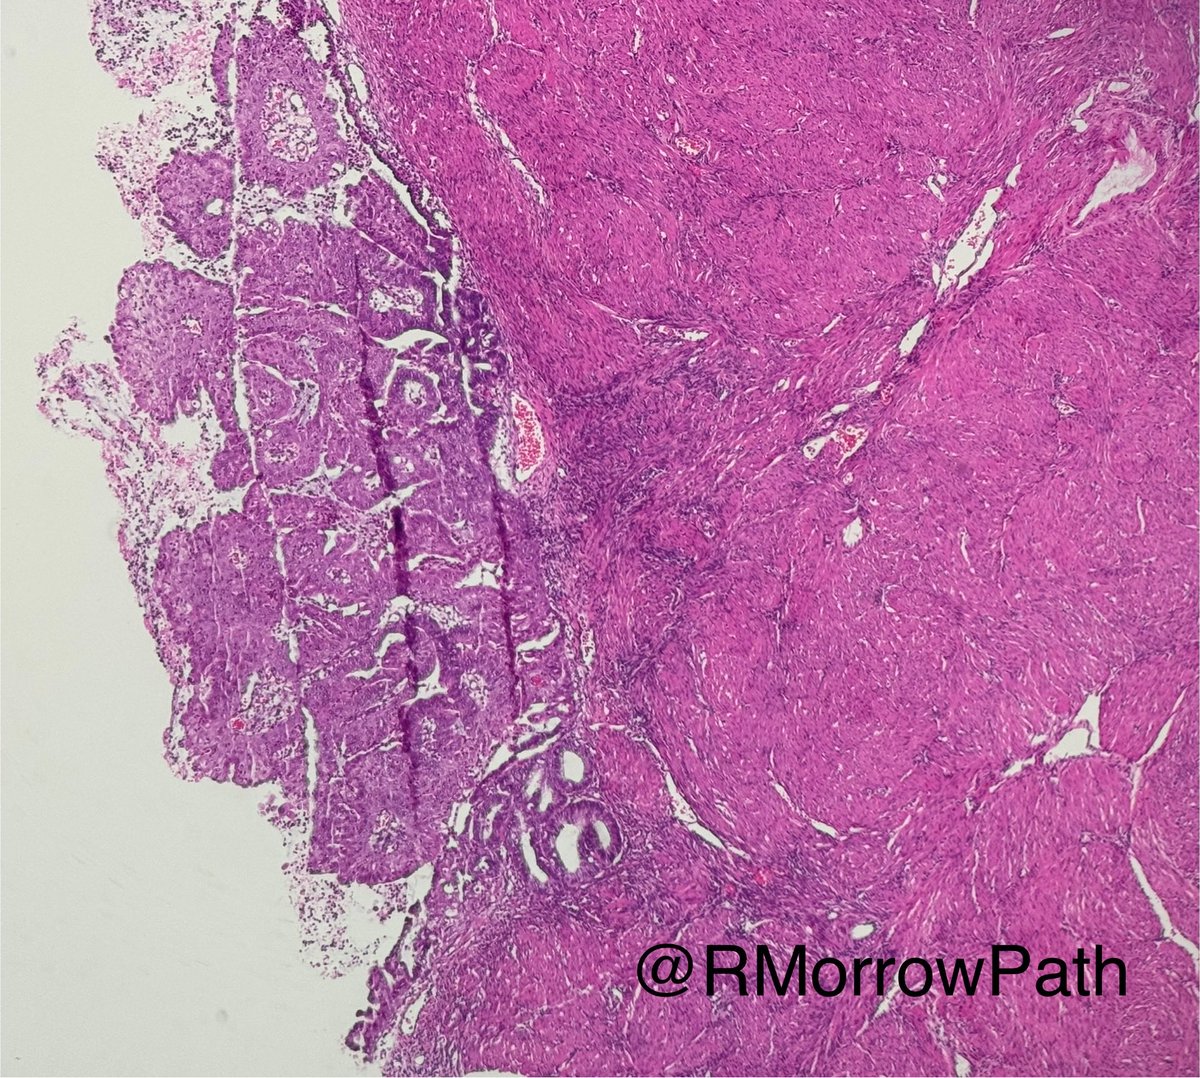

Older lady - pus filled endometrial cavity I sometimes see this pattern of LG Endometrioid Ca confused for a reactive process in curettes Clues: 🙈cribriform glands without myoeps 🙉 subtle nuclear atypia 🙊I reach for p16 (+), p40 (-) +/-mmr #gynpath #pathology